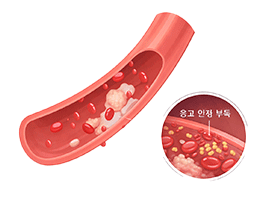

혈전증 (Thrombosis)